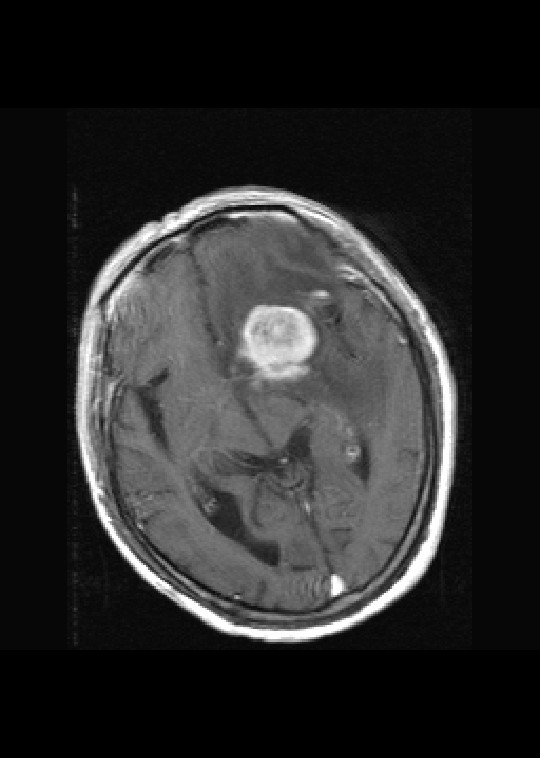

左侧基底节区病灶t1wi呈不均匀稍低信号,t2wi呈稍高信号,周围伴有水肿。增强扫描呈均匀团块样或者抱拳样明显强化,相邻的柔脑膜亦见线样强化。首先考虑淋巴瘤。可惜没有ct平扫,如果ct平扫病灶呈高密度,那么更支持pcnsl的诊断。

病理结果:(左额颞叶)非霍奇金淋巴瘤,b细胞性,弥漫性大b细胞型。免疫组化结果:cd45(lca) +,vimentin +,ck(ae1/ae3) -,ema -,cd3 -,cd20 +++,cd30 -,plap -,cd79a +,gfap -,alk -,s-100 -。

淋巴瘤,信号及强化方式较典型。灶周方广泛水肿相对较少见。长见识了。